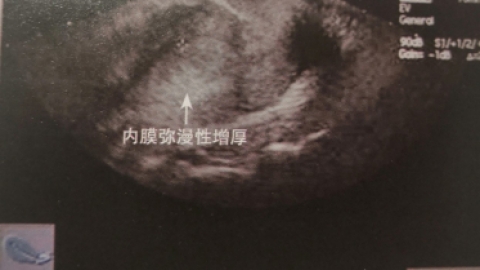

女性朋友出现子宫内膜薄的原因可分为全身和局部两种因素。出现子宫发育不良畸形也是出现女性子宫内膜偏薄的一个原因之一,此情况是长期以来被女性朋友忽略,在临床上有的患者会出现子宫造影不是倒梨形,甚至出现是细长条,这种情况出现子宫内膜薄是先天性,治疗起来相对比较难。正常的女性子宫内膜厚度是多少?女性出现子宫内膜薄吃什么好?